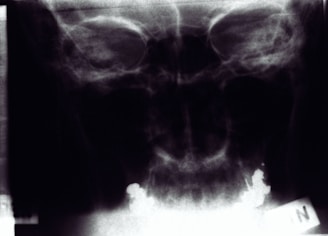

Panoramic Imaging

Comprehensive panoramic imaging solutions for thorough dental and maxillofacial evaluations.

Imaging Gallery

Explore our advanced CT and panoramic imaging services through visuals.